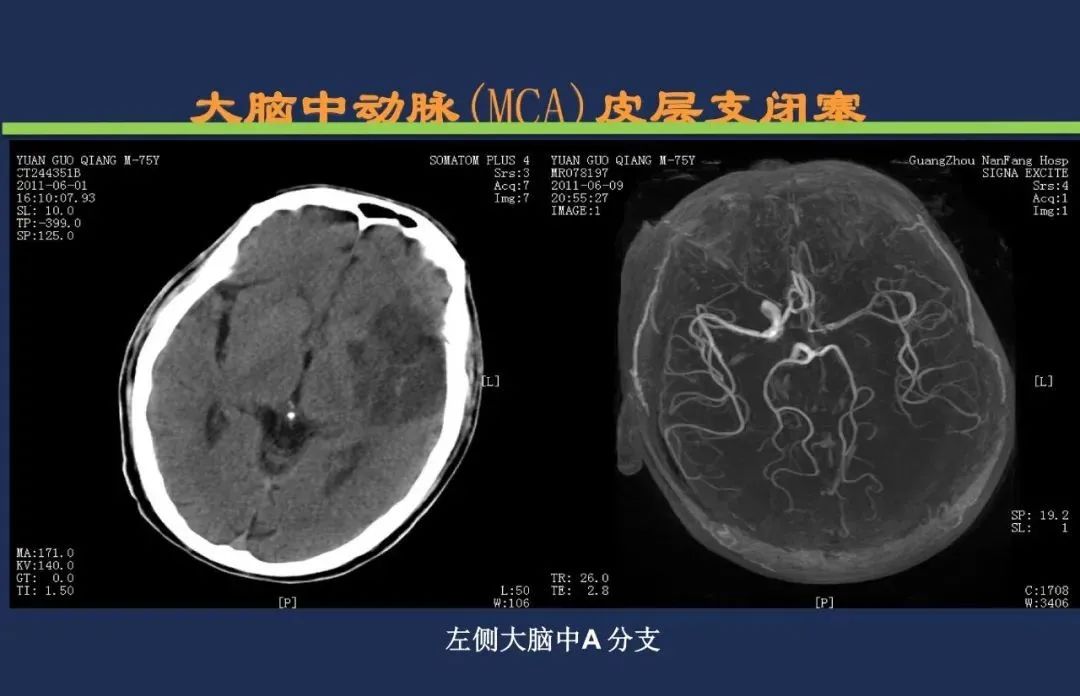

颈内动脉系统梗死颈内动脉大脑中动脉